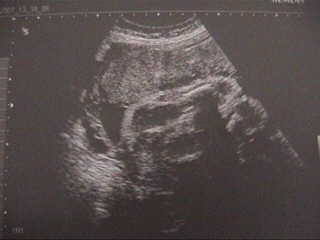

Szóval megjártuk a dokit is. :) Elöljáróban annyit, hoyg fotót holnap teszek, ha egyáltalán fog látszani valami belőle. (különben nincs is olyan nagyon sokat mutató fotó. )

Nos, a babával minden rendben. :D És velem is minden rendben. Mikor mondtam, hoyg elég gyakran és hosszaasan keményedik a hasam a doki attól tartott, hoyg nehogy meg legyek nyílva, de szerencsére szó sincs róla.

Mütyürke meg jól érzi magát. Befordult fejjel lefelé, aminek nagyon-nagyon örülök, a jobb oldalamon van a háta-gerince (pont mint Kriszta anno :) ) bár a pozíciót még megváltoztathatja.

A fejátmérője, a BPD: 75,9 mm, a combcsontja pedig 57,5 mm, ezek az adatok szerint Kismanóm már 29 hetes és pár napos (szóval pont annyi, mint ahogyan számontartom). A becsült súlya pedig 1465 g, ami a doki szerint tökéletes. Nincs semmi vizsgálat amit most csinálnom kell, semmi újat nem kell szednem, csak továbbra is a magzatvédő vitamint. Házi feladatként naponta 2-3 órás fekvőpihenést kell beiktatnom :roll: :roll: és ismét no-szex. :roll: :oops:

Itt van két képecske manóról, az egyiken profilból az arca eleje, az öklöcskéje és egy kicsi a lábából látszik, a másikon meg állítólag ismét a "lánysága". Én valóban, látok ott egy erősebb csíkot, valószínű, az az :D :